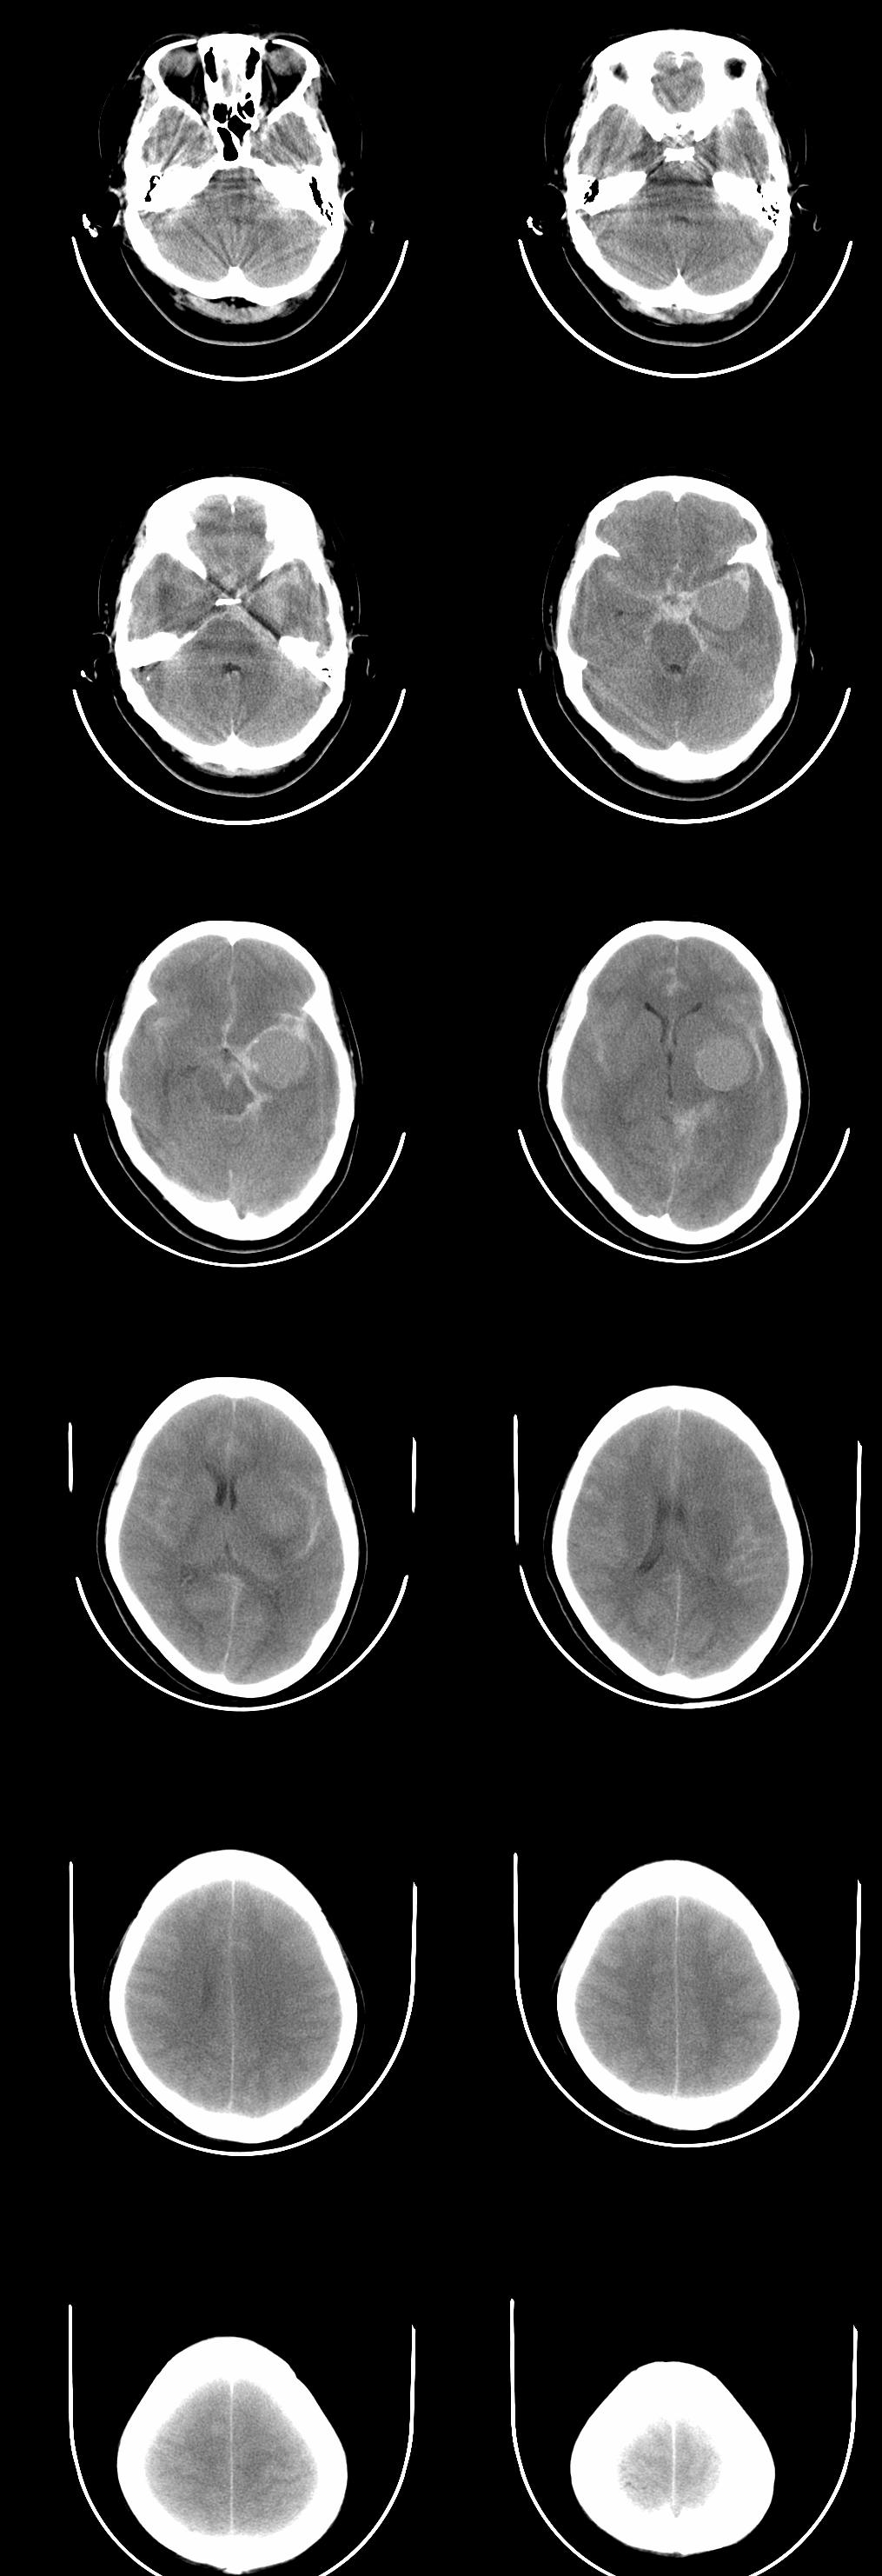

CT50520:帮忙看看,女,34岁,呼之不应,肢体活动障碍6 ...

CT50520:帮忙看看,女,34岁,呼之不应,肢体活动障碍6小...

1)左侧颞叶鞍上池及侧裂池旁占位性病变,不排除巨大动脉瘤可能;建议行进一步检查。2)蛛网膜下腔出血。

圆形,密度均匀,其内无钙化,应考虑动脉瘤破裂,伴蛛网膜下腔出血。

动脉瘤破了

脑膜瘤破裂,蛛网膜下腔出血

脑膜瘤 蛛网膜下腔出血